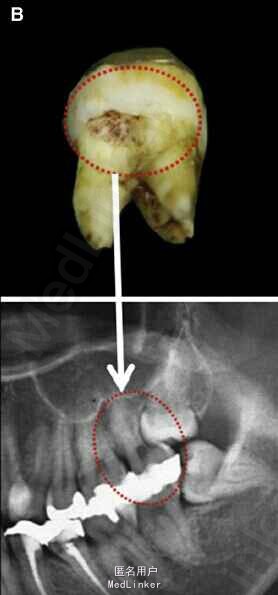

面部:凸面型,上下唇前突,上唇E线前3.5mm,下唇E线前9.5mm,闭唇时口周肌肉紧张。口内检查:双侧尖牙磨牙I类关系,左侧7锁合,覆盖4.5mm,覆合1mm,中线正,上颌拥挤度12.5mm,下颌拥挤度8.2mm。全景片示4个第三磨牙均阻生,怀疑上颌第二磨牙远中面因8阻生有牙根吸收,下颌8近中倾斜阻生更严重,右下6、左下4和5都行了RCT并大面积充填。头影测量示骨性I类,高角,下切牙唇倾。无TMJ症状,只是咀嚼测试时,右侧(非锁合侧)较左侧速度更快且更稳定。

诊断:安氏II类1分类,双颌前突,牙列严重拥挤,左下7锁合,双侧上7牙根吸收,四颗第三磨牙阻生 治疗目标:减少唇的突度及前牙拥挤,扶正4颗阻生的第三磨牙,达到良好的面部美观和功能咬合。 治疗:上颌拔除2颗5和2颗7(不拔4的原因为左上4为正常牙,左上5大面积充填;右上4形态较右上5好。因拔除了坏牙保留了健康牙齿,但是拔5不利于前牙的内收,所以于上后牙56之间植入了支抗钉加强支抗,辅助内收前牙。拔7原因为两颗7远中面均有牙根吸收且有大面积充填),下颌左侧拔除5和7(左下5根管治疗且根尖阴影,拔除左下7原因为严重锁合,改正困难且容易导致上下磨牙的伸长加重II类高角面型),右侧拔除根管治疗且大面积充填后的6;分别竖直4颗近中倾斜阻生的8,整个疗程39个月,四颗8成功的代替6或7。双侧I类尖牙关系,左侧磨牙I类关系,右侧磨牙完全远中关系。唇突度改善,全景片可见达到可接受的牙根平行度,4个8完全萌出直立。以前因为锁合导致的两侧咬合不对称没有了。